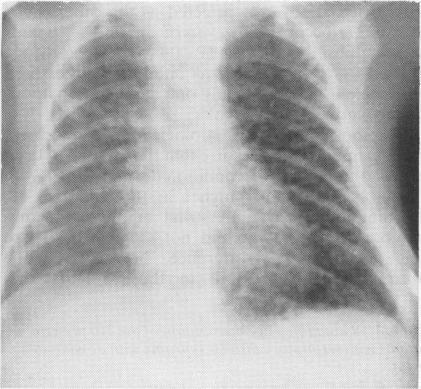

Pulmonary interstitial emphysema.

Forty one of 210 preterm infants ventilated for respiratory distress syndrome in a three year period had radiological evidence of pulmonary interstitial emphysema. The development of this condition was significantly associated with malpositioning of the endotracheal tube in a main bronchus and the use of high peak pressure ventilation. Pulmonary interstitial emphysema was associated with a significant increase in the number of pneumothoraces, intraventricular haemorrhages, and the need for prolonged respiratory support, but did not increase mortality. Although in 12 infants in whom fast rate ventilation was used there was a significant reduction in the number of pneumothoraces, outcome was not altered in any other way. Fast rate ventilation may be of greater benefit if initiated before the development of pulmonary interstitial emphysema.